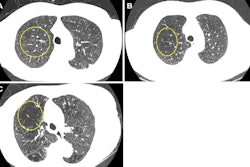

Low-dose CT images show examples of screen-detected pulmonary nodules (arrows) where the deep-learning algorithm provides a more accurate malignancy risk estimation than the Pan-Canadian Early Detection of Lung Cancer (PanCan) model on axial (top), coronal (middle), and sagittal (bottom) planes. (A) Image shows a 9.7-mm malignant nodule (arrows) with a high deep-learning risk score (32.3%) and low PanCan risk score (3.2%) in a 74-year-old male participant diagnosed with squamous cell carcinoma. (B) Image shows a 6.8-mm malignant nodule (arrows) with a high deep-learning risk score (15.9%) and low PanCan risk score (1.2%) in a 71-year-old male participant diagnosed with adenocarcinoma. (C) Image shows a 19 mm benign nodule (arrows) with a low deep-learning risk score (4.7%) and high PanCan risk score (32.7%) in a 50-year-old female participant. Additional PanCan input features used in the model were retrieved from original trial records, as follows: (A) negative for family history of lung cancer, negative for emphysema, negative for spiculation, negative for upper lobe location, nodule count: four; (B) negative for family history of lung cancer, negative for emphysema, negative for spiculation, negative for upper lobe location, nodule count: two; (C) negative for family history of lung cancer, positive for emphysema, negative for spiculation, positive for upper lobe location, nodule count: one. Images and caption courtesy of the RSNA.